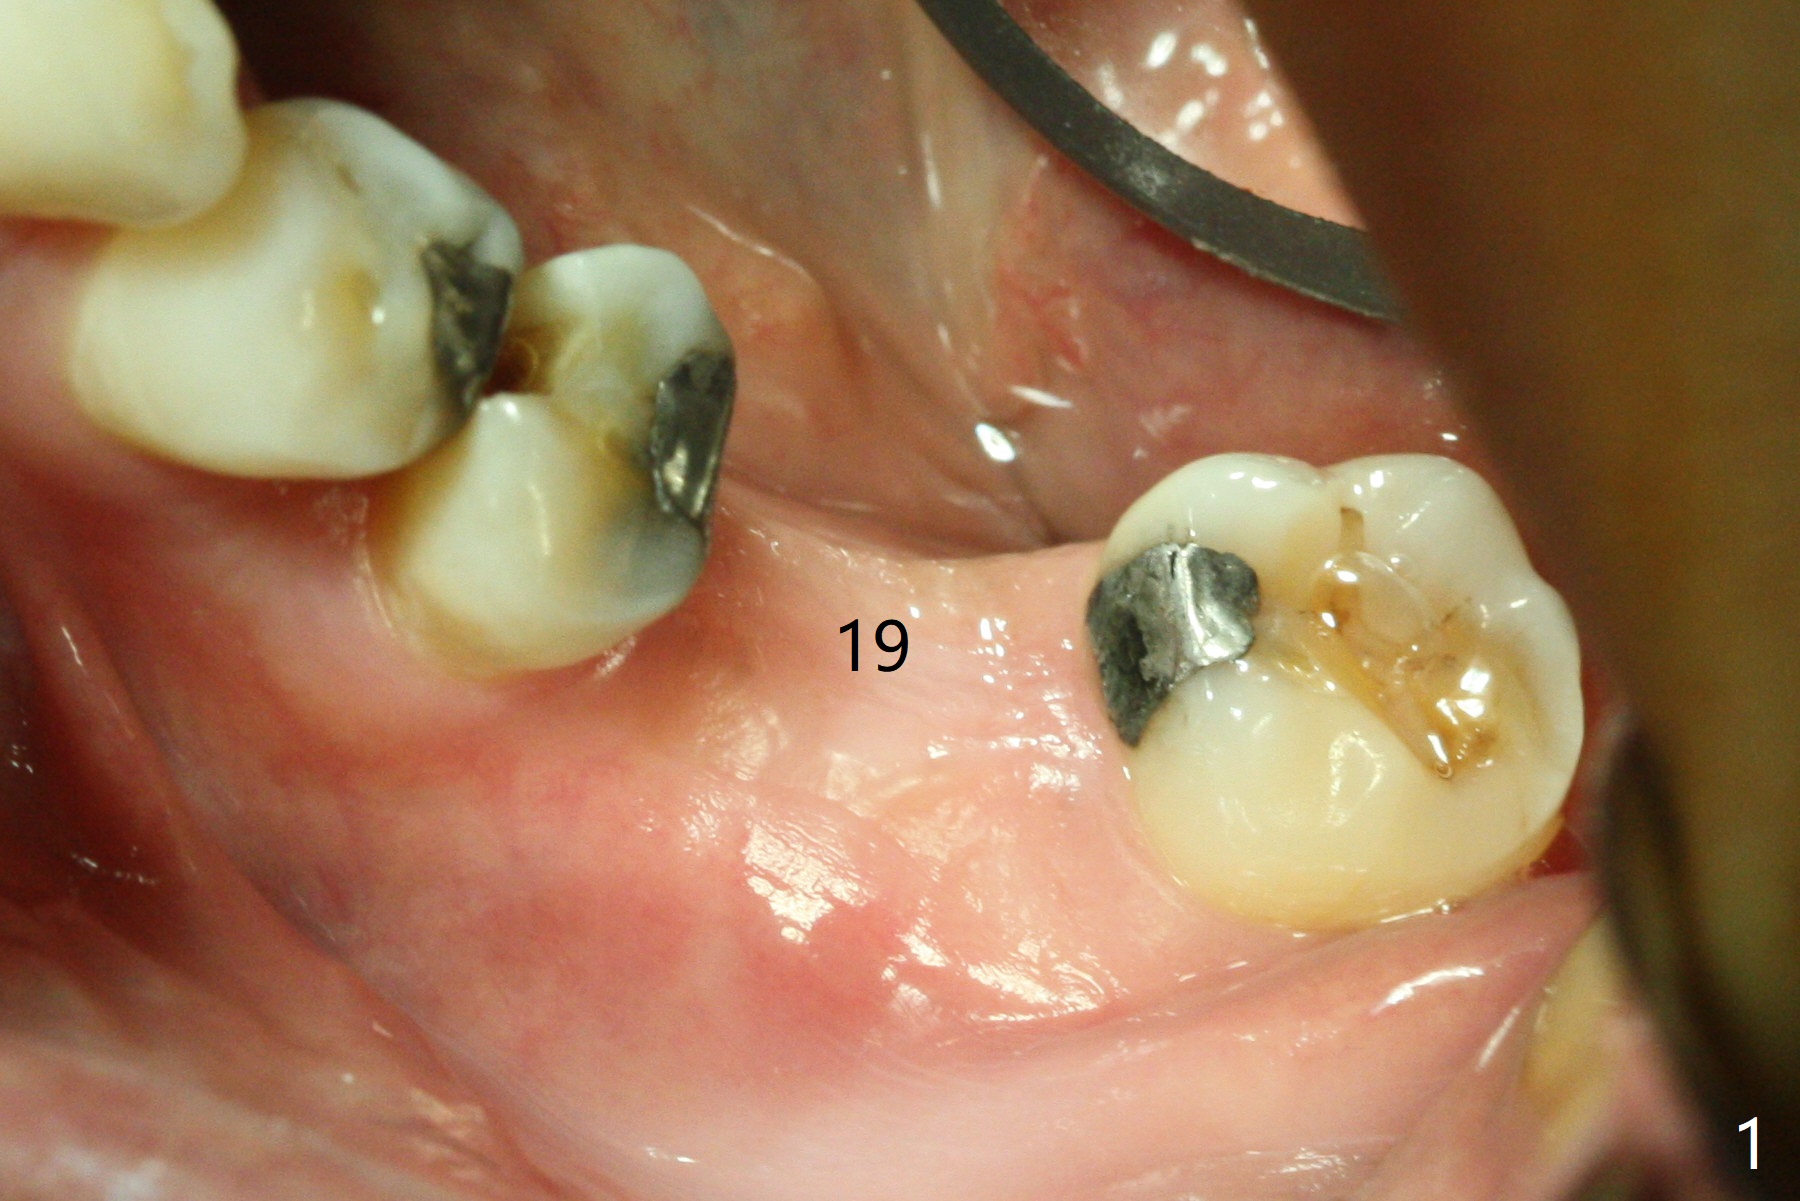

The ridge at #19 is slightly atrophic 5 months post socket preservation (Fig.1). The bone is long enough to hold a 11.5 mm long implant. There is no difficulty in inserting the corresponding drill (4.5x11.5 mm) into the metal sleeve, but the lower right posterior teeth prevent the implant handpiece from going downward completely when the handpiece accesses lingually. Because of the extra manipulation, a 5x10 mm implant achieves insertion torque of ~ 20 Ncm (Fig.2). The implant seems to be seated in the middle of the ridge (Fig.3). The bone density mesial to the implant increases 5 months postop (Fig.4), whereas that distal to the implant remains low 9 months postop (Fig.5). Bitewings taken 2.5 months post cementation (1 year postop, Fig.6,7) show subcrestal placement of the implant (advantage of guided surgery). The implant appears to be well protected; the crestal bone seems to cover the implant plateau. There will be little chance of thread exposure over years of use. The trabecular pattern around the implant is similar to that around the roots of the tooth #30 one year 7 months post cementation (2 years 4 months postop, Fig.8).